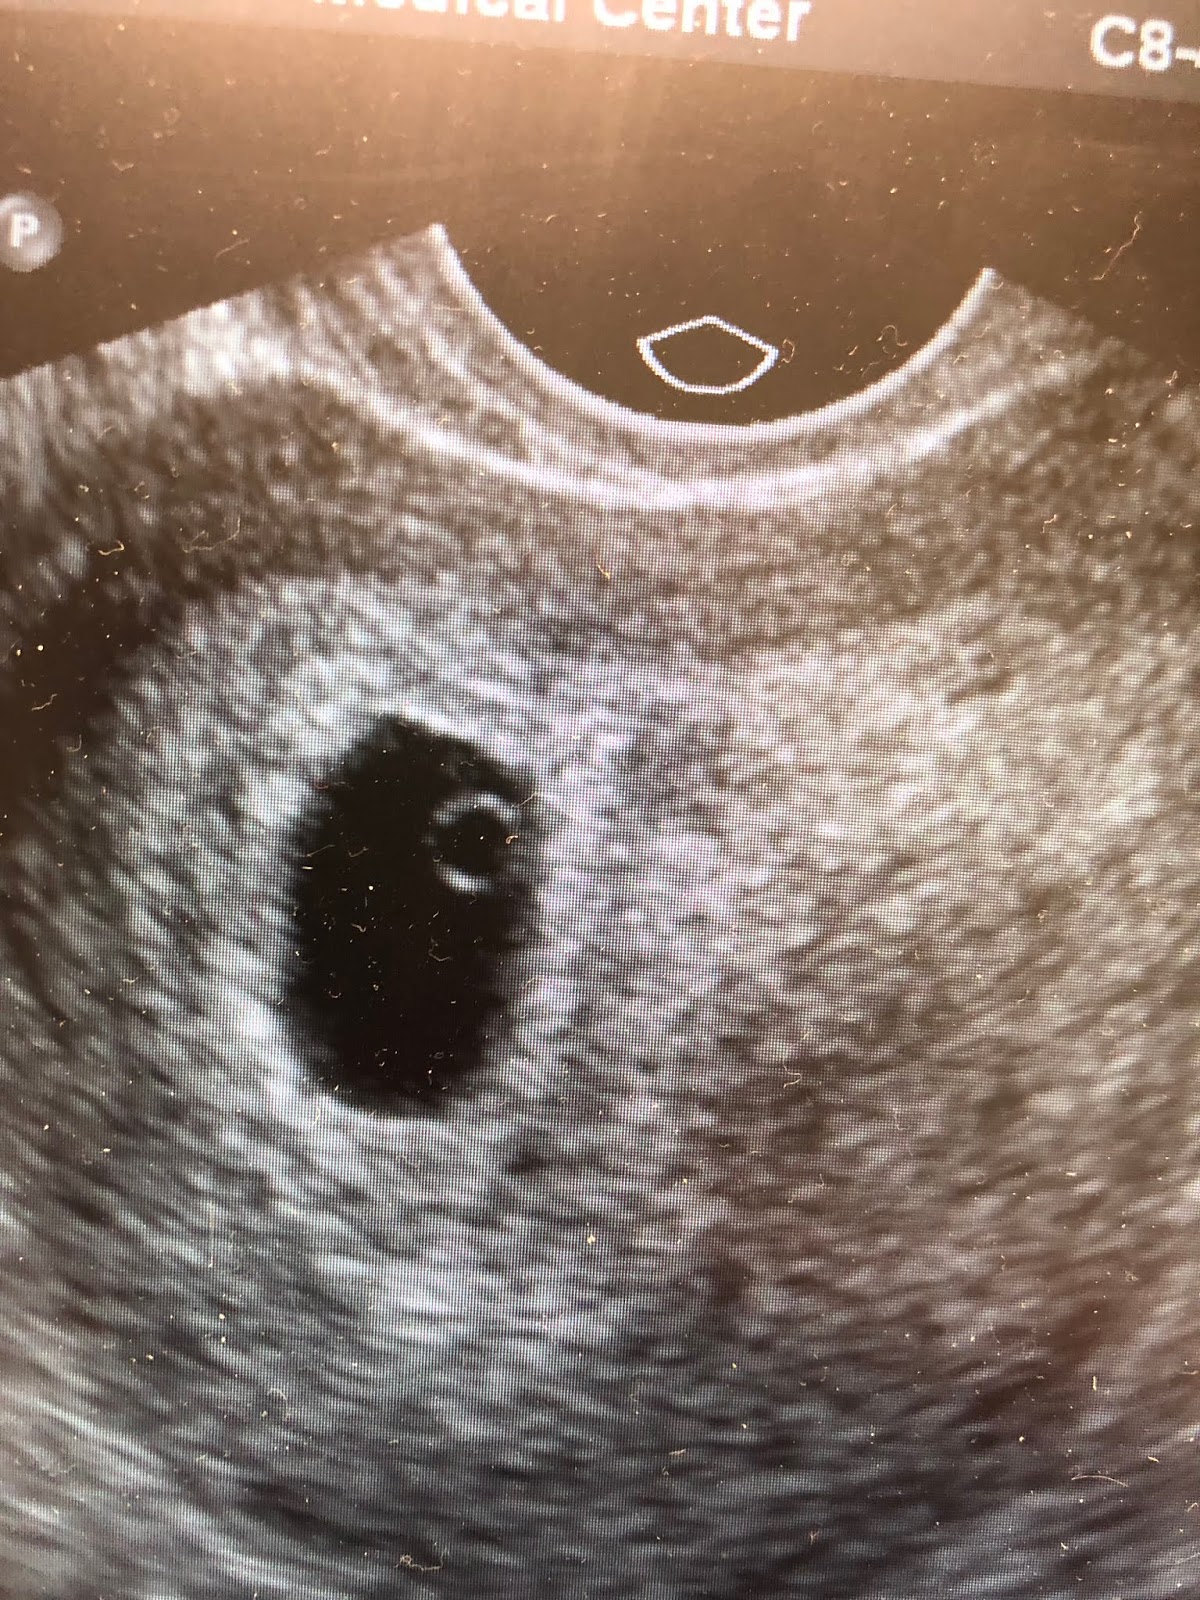

My cute little intra-uterine yolk sac:

We immediately went into the registration area, where there was a full waiting room, but luckily he knew all the doctors and nurses, so they took me right in. Within 10 minutes of arriving, I had my vitals done, I had seen the doctor (who was actually co-interns with Sarath, which worked out nicely), gotten an IV and blood work sent off. I was then quickly wheeled into ultrasound. I know that ultrasound techs aren't aloud to say anything about what they say, but this was the most nerve wracking part. I was trying to study the US techs face to see if it was good or bad. I kept mouthing to Sarath what he saw, but all he could say was that he saw "something". Something. Something good? Something bad? I needed to know immediately. Thankfully by the time we got wheeled back into the room from ultrasound, my nurse came in right away with a big smile and said the doctor would be right in, but not to worry. I was thinking maybe that was a good sign. She wouldn't say that if something terrible was happening right? Anyways, literally about 2 minutes later, our doctor came in, told me that my ultrasound was normal for 5w4d, that they saw an appropriate gestational sack with a yolk sac and fetal pole. My labs were also normal with no anemia and a bHCG level of >33K. So, all that was great and I got sent home (after less than 2 hours total, which is pretty amazing...thanks UCI ER!). I know I should feel better, but ugh I am still so scared.